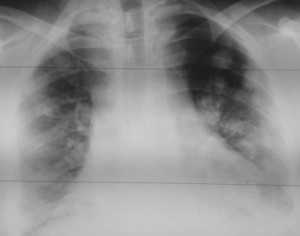

Как выглядят метастазы в легких на рентгене? Слева — узловые образования у пациента с раком яичка. Справа - метастазы рака яичников гематогенного характера с выраженным опухолевым лимфангиитом (обратите внимание на деформированный сетчатый, линейный характер легочного рисунка).

Лимфогенные метастазы на рентгене и КТ выглядят как множественные мелкие очаги с диссеминированным распространением, локализованные в междольковых перегородках, в плевральных листках. Вокруг можно видеть характерную картину ракового лимфангиита. Кроме того, практически всегда выявляются патологически измененные и увеличенные лимфатические узлы средостения. Лимфогенное метастазирование необходимо дифференцировать с милиарным туберкулезом, саркоидозом. Иногда это требует привлечения Второго мнения.

Лимфогенные метастазы проявляются увеличением лимфатических узлов средостения в сочетании с мелкоочаговой диссеминацией с очагами до 2-3 мм в диаметре вблизи плевры и в междольковых перегородках, а также по ходу бронхов и сосудистых пучков.